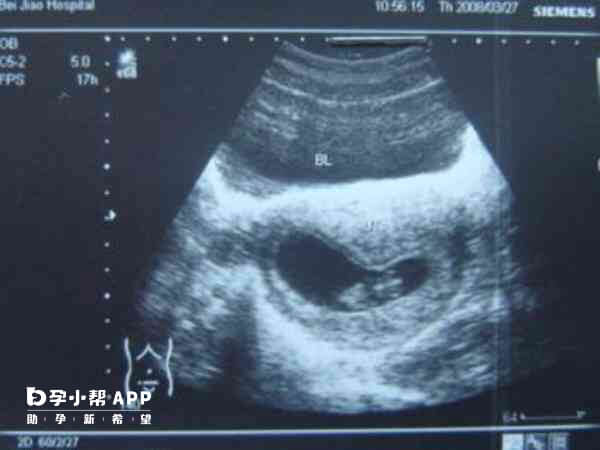

1、B超检查

B超检查作为妇科最常规检查,可以清楚的观察到子宫附件的具体状况。因此女性朋友想要确定自己是否患有卵巢早衰,第1件事情就是要进行B超检查,而且一般要在月经干净后3~7天内进行检查。若是女性的卵巢又小又杂乱,而且没有看到卵泡,那基本可以确诊为卵巢早衰。